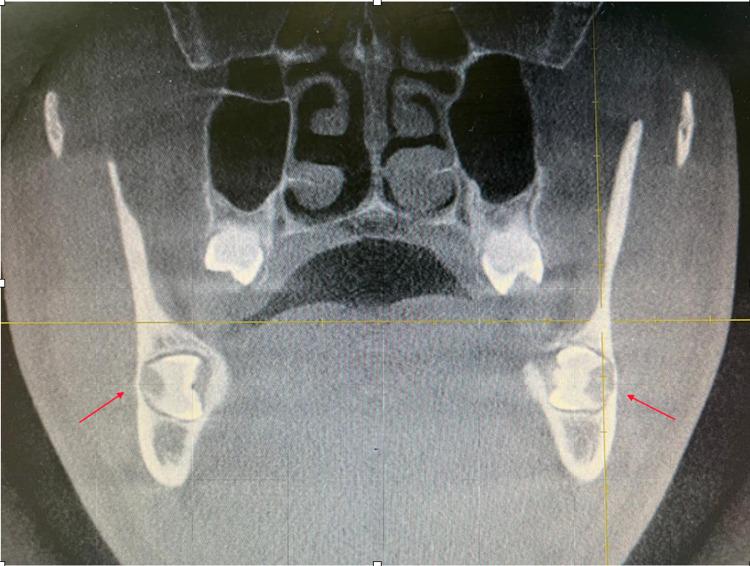

Symmetrical horizontal impacted bilateral mandibular third molar in lingo-buccal direction is a rare type of impacted teeth. When a tooth cannot erupt and fails to achieve a normal function and occlusion during its chronological age of eruption, it is called an impacted tooth. In this paper, a case of a male patient aged 20 years old who had bilateral horizontally impacted lower third molar which was noticed in a routine screening panoramic radiograph and confirmed with cone beam computed tomography (CBCT) imaging and referred to the oral maxillofacial surgical center for surgical removal of the impacted teeth in order to avoid late complications is discussed.

摘要

双侧下颌第三磨牙在舌颊向呈对称性水平阻生是一种罕见的阻生牙类型。当一颗牙齿在其正常萌出年龄时不能萌出且无法实现正常功能和咬合时,就称为阻生牙。本文讨论了一例20岁男性患者,其双侧下颌第三磨牙水平阻生,在常规筛查全景X线片上被发现,并经锥形束计算机断层扫描(CBCT)成像证实,随后转诊至口腔颌面外科中心进行手术拔除阻生牙,以避免后期并发症。